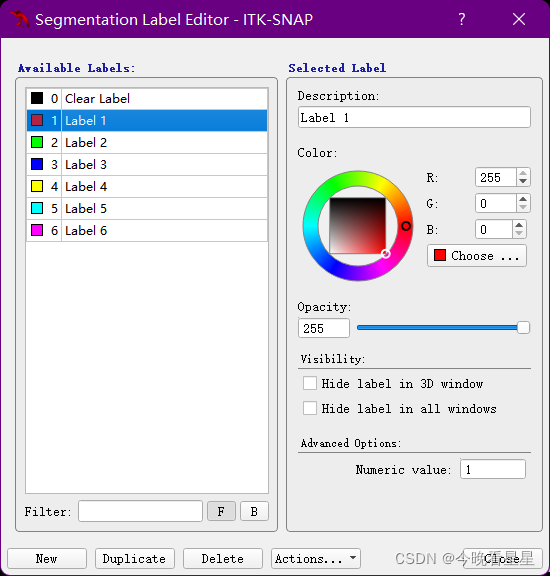

Undo撤销,Redo重做Foreground Label与Background Label是不同标注之间的关系

1.3.1 个性化标注

Active Label为激活的标签,表示当前使用的标柱类型,此时选择label 1为红色,说明使用红色进行标注paint Over为允许标注的范围,All labels允许对所有的标签进行标注,包括覆盖之前的标注;All visiable label是对所有可见的标签进行标注,如图,红色所在的位置则不能标注,

paint over续:使用Active Label=Label1; paint Over=Clear Label标注时,只允许对没有标注的区域标注,如图,同样的,如果paint over=Label1(red), active label = label3则蓝色只能在红色上标注

Open Segmentation打开标注的文件,标注的文件为.nii格式,可以直接进行拖拽的方式来获取标注Save Another Segmentation保存标注的图像,格式为nii, 保存的标注格式,可以直接拖拽到原始图像中Unload Segmentation可以将加载的标注去掉Export as Surface Mesh将标签保存为vtk文件Label Editor对Label的相关属性进行编辑